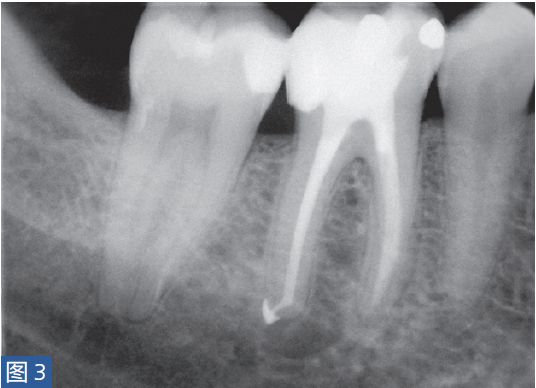

症状性根尖周炎(SAP symptomatic apical periodontitis)从牙髓炎过渡到根尖周炎(图2和3)的发生速度非常快,牙齿表现可能从正常到对冷、热和电刺激的反应越来越强。当牙髓已经完全坏死时,通常会显示对牙髓电活力测试无反应。牙齿可能会有伸长感,用手指或口镜柄施加压力或者振动牙齿会触发非常严重的疼痛。放射学检查可能存在透射区及根周膜间隙增宽,通常硬骨板和牙周韧带没有病理学特征。

图2:46 牙齿SAP。术前X 线片,该牙齿在其他医生处已行龋齿治疗。患者诉牙齿有明显的咬合痛以及强烈的冷热刺激敏感症状。放射学检查,近中根根周膜间隙略增宽。

图3:46 牙齿SAP。根管治疗6个月后。